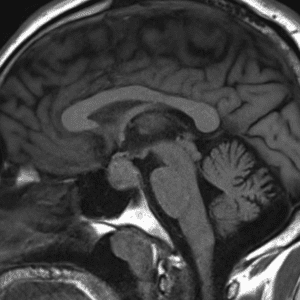

Case #39

Ectopic posterior pituitary